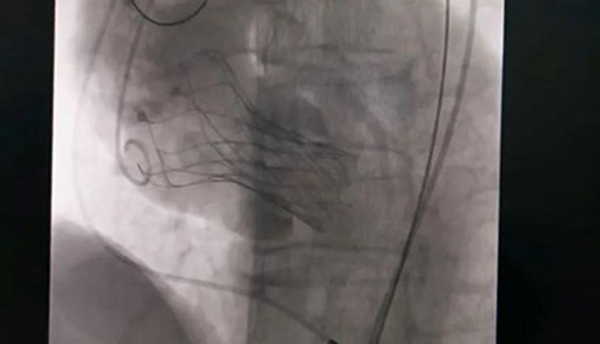

人工瓣膜置入中。重慶西區醫院供圖

10月18日,該患者實施手術,在新橋醫院專家的指導下,心血管內科主任宋明寶帶領團隊把瓣膜置入心臟。